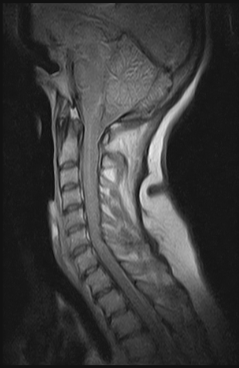

Clínica Ressonância Magnética da Coluna

RM BrasilSe quer encontrar uma clínica ressonância magnética da coluna que ofereça preços acessíveis, entre em contato conosco, da RM Brasil, sua melhor opção.Visamos obter a excelência e, para isso,...